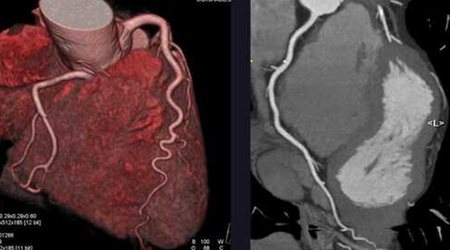

سی تی آنژیوگرافی 🔗

CT Angiography